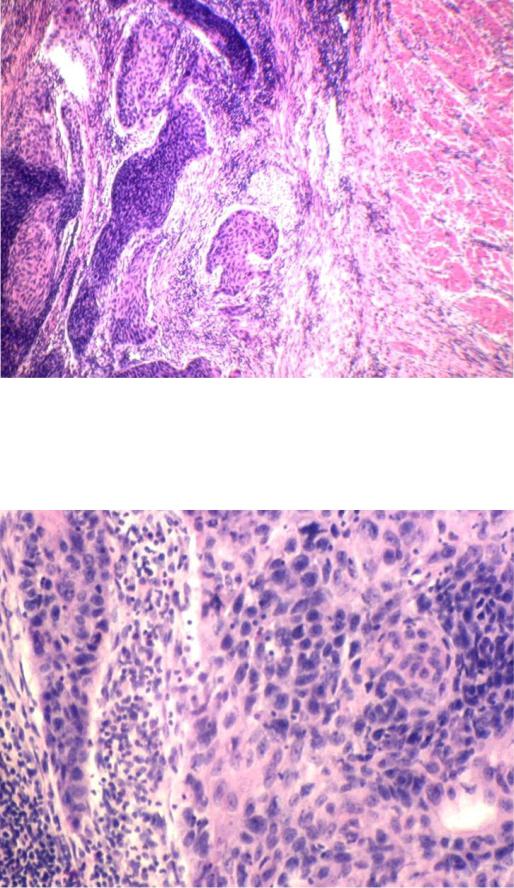

Фотографии опухоли медуллярной аденокарциномы

Раздел: Снимки-откровения